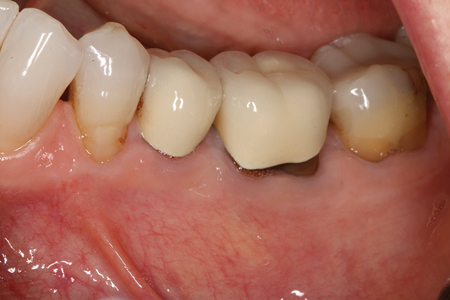

Dental Tourism: Caveat Emptor

Viewpoint FIGURE #1 alternate text for this image

Many of our patients are attracted to the allure of cheaper dental treatment abroad. Tooth #36 in the accompanying radiograph (Fig. 1) and photo (Fig. 2) is an example of such a case. Unfortunately in this case, almost every possible iatrogenic endodontic mishap was encountered. This treatment is substandard and if done in Canada the … Read more